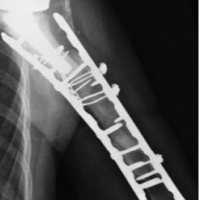

The post-operative course was uneventful. Active range-of-motion (ROM) exercises were initiated after the splint was removed. At 3 months, plain radiographs confirmed bone union, and the patient had resumed daily and social activities without restriction. At 12 months (Figs. 4 and 5), she reported no wrist pain and had returned to normal activities without limitations.

Figure 4: Radiographs at the 12-month follow-up demonstrate bone union with proper anatomical alignment and no pisotriquetral degenerative changes.

Radiographs demonstrated complete union and proper alignment. The implant remained well-positioned, with no sign of loosening or migration, and no degenerative changes were observed in the pisotriquetral joint.